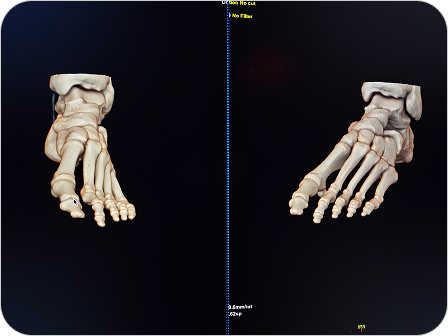

Reconstrucción 3D en Tomografía

Es una técnica avanzada que permite convertir las imágenes obtenidas por tomografía computada en modelos tridimensionales. Estas reconstrucciones permiten visualizar estructuras anatómicas de forma realista, facilitando diagnósticos más precisos y una mejor planificación quirúrgica o terapéutica.

Las reconstrucciones tridimensionales a partir de tomografía computada permiten visualizar la anatomía de forma realista y precisa, facilitando diagnósticos y cirugías complejas.

¿PARA QUE SE UTILIZA?

- Evaluación detallada de fracturas complejas, articulaciones y columna vertebral.

- Estudio anatómico previo a cirugías (traumatológicas, maxilofaciales, cardiovasculares).

- Visualización de vasos sanguíneos, tumores o malformaciones desde distintos ángulos.

- Planificación prequirúrgica más segura y personalizada.

- Educación médica y explicación visual a pacientes.

¿POR QUÉ ES UN ESTUDIO DESTACADO?

- Imágenes más claras y comprensibles para médicos y pacientes.

Facilita una mayor precisión diagnóstica. - Permite una visión global y tridimensional de la anatomía.

- Complemento ideal para especialidades como traumatología, neurocirugía, cirugía maxilofacial y oncología.

Reconstrucción 3D en Tomografía

Es una técnica avanzada que permite convertir las imágenes obtenidas por tomografía computada en modelos tridimensionales. Estas reconstrucciones permiten visualizar estructuras anatómicas de forma realista, facilitando diagnósticos más precisos y una mejor planificación quirúrgica o terapéutica.

Las reconstrucciones tridimensionales a partir de tomografía computada permiten visualizar la anatomía de forma realista y precisa, facilitando diagnósticos y cirugías complejas.

¿PARA QUE SE UTILIZA?

- Evaluación detallada de fracturas complejas, articulaciones y columna vertebral.

- Estudio anatómico previo a cirugías (traumatológicas, maxilofaciales, cardiovasculares).

- Visualización de vasos sanguíneos, tumores o malformaciones desde distintos ángulos.

- Planificación prequirúrgica más segura y personalizada.

- Educación médica y explicación visual a pacientes.

¿POR QUÉ ES UN ESTUDIO DESTACADO?

- Imágenes más claras y comprensibles para médicos y pacientes.

Facilita una mayor precisión diagnóstica. - Permite una visión global y tridimensional de la anatomía.

- Complemento ideal para especialidades como traumatología, neurocirugía, cirugía maxilofacial y oncología.